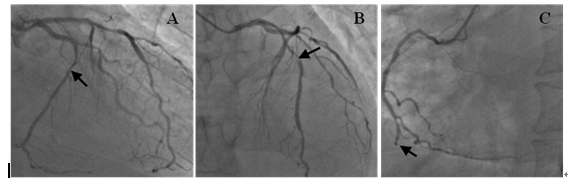

于入院后第2天行冠脉造影术,结果显示:LAD 近中段 50-90% 狭窄;D1/D2 50%狭窄; LCX中段60%;OM1 80%; OM299%;RCA 近段 50% 狭窄;中段75%;远段100%狭窄(图1)。

图1 左右冠脉造影